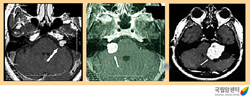

뇌하수체 거대선종의 뇌 자기공명영상촬영 소견

2009.08.21

청신경초종의 뇌 자기공명영상 촬영 소견

2009.08.21